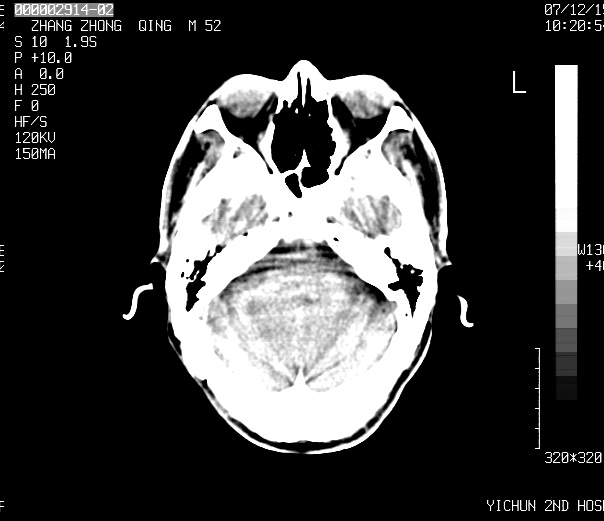

标题: CT11173:请会诊 男 52

不知ct值约多少,考虑四叠体池内脂肪瘤.

不知ct值约多少,考虑四叠体池内脂肪瘤.支持!

四叠体池脂肪瘤可能

1、四叠体脂肪瘤;

2、双侧额、顶部硬膜下积液。

头痛二年余,ct值-86.8hu.